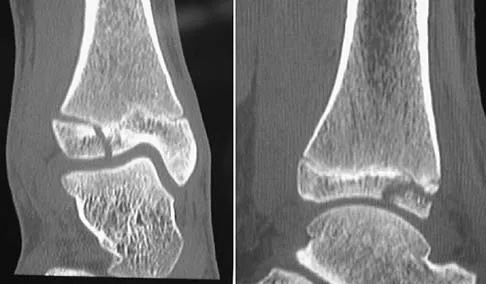

Question 53 High Yield

A 13-year-old girl injures her ankle playing soccer. Radiographs reveal a displaced Tillaux fracture. CT scans are shown in Figure 25. What is the most important consideration for appropriate management?

Detailed Explanation